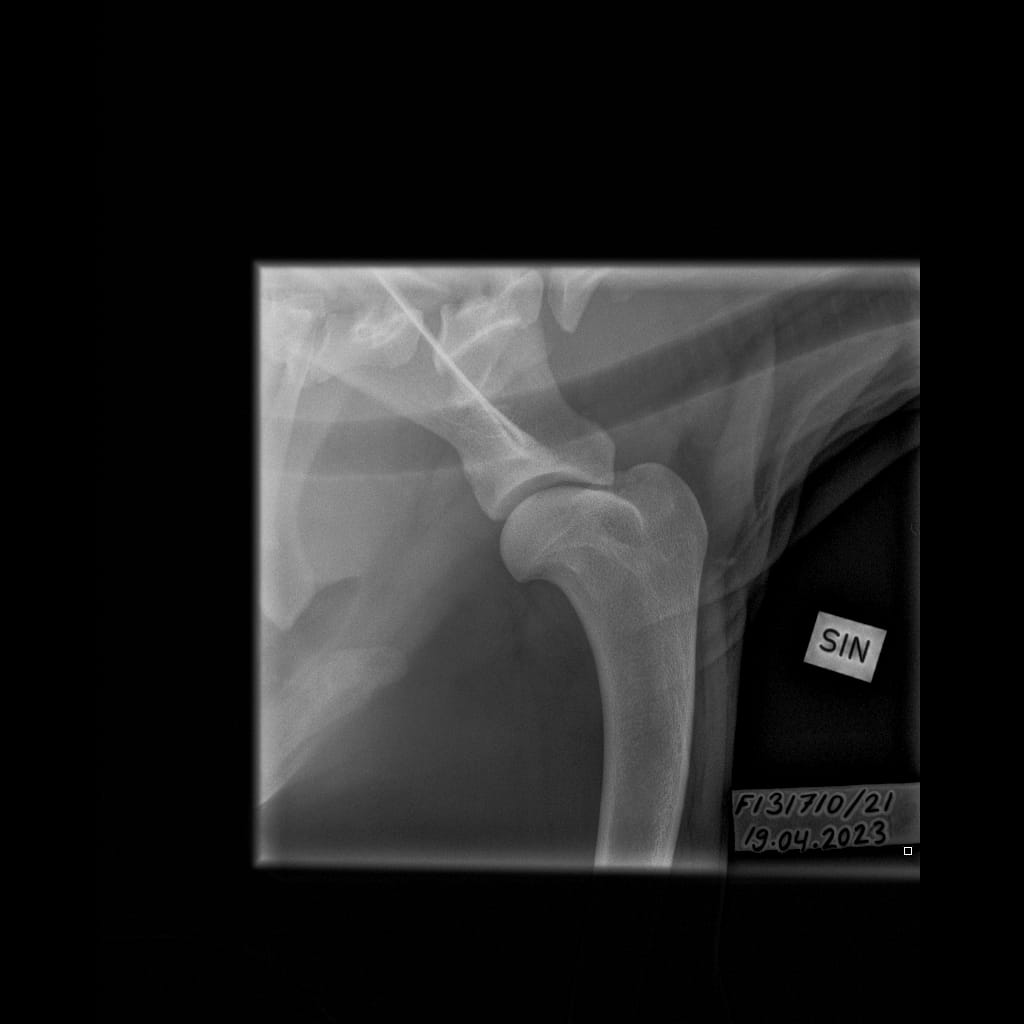

Eturaajat -Olkanivel ML -6.11.2023-16_02_18-265